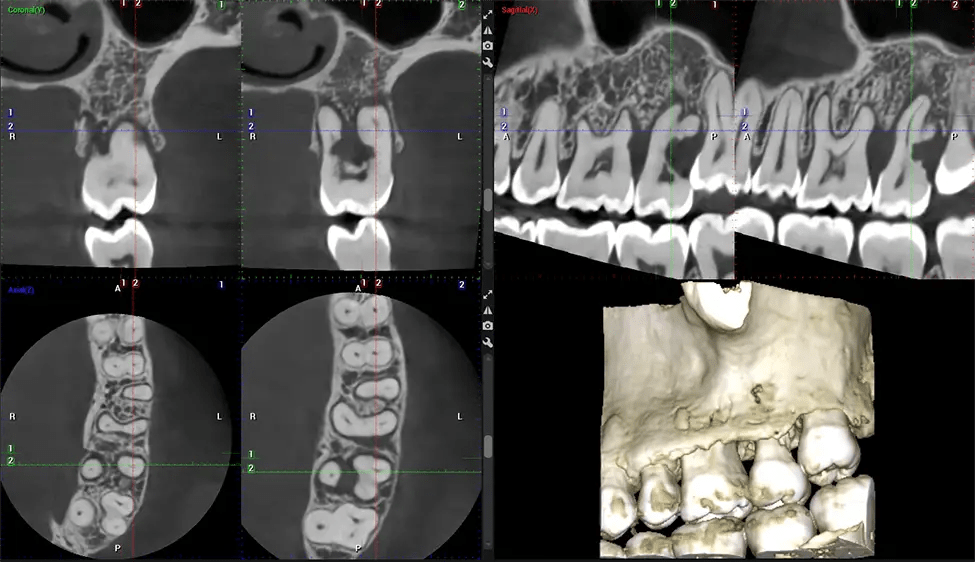

La tomografía computarizada de haz cónico (CBCT) es una técnica de imagen avanzada utilizada en odontología y cirugía maxilofacial para obtener imágenes detalladas en 3D de las estructuras orales y maxilofaciales. En Dr G Dental Studio, nuestros escáneres CBCT utilizan un haz de rayos X en forma de cono y un detector especializado para capturar imágenes desde diferentes ángulos. Luego, una computadora combina estas imágenes para crear una representación 3D de la anatomía oral del paciente.

Esta exploración 3D, llamada tomografía computarizada de haz cónico, le brinda a su dentista una imagen más completa de su anatomía bucal y sus procesos patológicos que una radiografía tradicional. A diferencia de las radiografías convencionales, que capturan una imagen 2D de la boca desde varios ángulos, una exploración 3D toma varias radiografías digitales para una imagen. Proporciona una vista completa de la mandíbula, los dientes, los nervios y los tejidos blandos. Esta vista mejorada permite a los dentistas detectar problemas menores que no son visibles en las exploraciones 2D tradicionales, como muelas del juicio impactadas o fracturas óseas en la cavidad sinusal.

Existen muchos beneficios al utilizar la tecnología CBCT, especialmente en comparación con el formato tradicional de rayos X 2D. Una de las ventajas más importantes de las exploraciones CBCT es que proporcionan mucha más información que las radiografías tradicionales. Una exploración le permite a su dentista ver imágenes desde todos los ángulos de su mandíbula y boca, incluidos los senos nasales, la cavidad nasal, los pómulos y otras áreas circundantes. Esta información adicional ayuda a su dentista a elaborar un plan de tratamiento integral que aborde todos los aspectos de su salud bucal.

Otro beneficio importante es que las imágenes 3D proporcionan imágenes más precisas de la estructura ósea. Estas imágenes son más detalladas y le brindan un diagnóstico más preciso. Un diagnóstico preciso significa un mejor tratamiento para usted.

Después del proceso de escaneo, las imágenes de rayos X capturadas son procesadas por el software CBCT, que aplica algoritmos para reconstruir una imagen 3D detallada del área escaneada. El software recopila estas imágenes de rayos X individuales y crea una representación digital en 3D de la anatomía del paciente. El dentista o el radiólogo pueden ver y analizar la imagen CBCT 3D reconstruida. Esta imagen se puede manipular, rotar y acercar o alejar para examinar estructuras específicas y evaluar la condición del paciente.